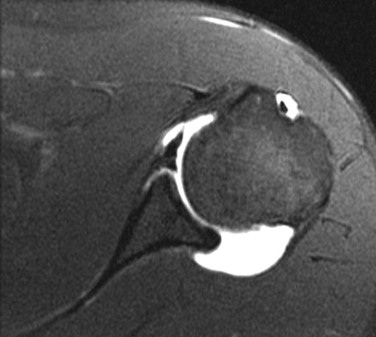

Although conventional MRI is established as the imaging modality of choice in the evaluation of shoulder impingement syndrome, MRA is accepted as the method of choice for the evaluation of glenohumeral instability.22,23 Many of the lesions associated with instability are subtle and may undergo partial healing. This situation, coupled with the fact that the normal anatomic structures of the shoulder lie in close proximity, can make the diagnosis of these lesions difficult even with high-quality conventional MRI.58-62 MRA, on the other hand, is performed by distending the joint with fluid (saline solution or dilute gadolinium), which more accurately depicts subtle labral tears, cartilage and ligamentous abnormalities, and partial-thickness tears of the undersurface of the rotator cuff. The standard injection technique for MRA of the shoulder is described in previous sections. About 12 to 14 mL of gadolinium diluted 1 : 200 with normal saline solution or 1% lidocaine is injected. Imaging protocols vary, but a standard set of imaging sequences typically includes T1-weighted images with frequency-selective fat saturation in the axial, oblique sagittal, and oblique coronal planes. The T1-weighted images have a high signal/noise ratio, resulting in the anatomic detail that is critical in detecting the subtle lesions associated with glenohumeral instability. A T2-weighted sequence performed in the oblique coronal plane is the most important sequence for depicting rotator cuff abnormalities. A T2-weighted sequence may also be helpful in detecting other pathologic processes, such as a paralabral cyst or bone marrow edema (Fig. 44-7, A and B). The ABER view may be added to the standard imaging protocol for any patient thought to have an anterior labral pathologic process.54

MRI and MRA are the main imaging modalities used in the evaluation of a patient with glenohumeral instability.22,23 Even with 3-tesla magnets, MRA demonstrated superior sensitivity compared with routine MRI in a study of 150 consecutive examinations for detecting SLAP lesions and labral tears.138 Joint distention with fluid outlines and separates the normal anatomic structures, allowing more accurate depiction of subtle lesions (Fig. 44-36). CT imaging with sagittal and coronal reconstructions remains the study of choice for detecting and depicting the size and location of a fracture fragment of the anteroinferior glenoid rim (see Fig. 44-4), which can be useful in presurgical planning in patients with large osseous Bankart lesions. As previously stated, MDCT arthrography is accurate for detecting instability lesions and very useful for patients who cannot undergo MRA or lack access to MRI services. The addition of MRI stress views, such as the ABER view (see Fig. 44-37, C), may improve visualization of a nondisplaced tear in the anterior inferior labrum.54